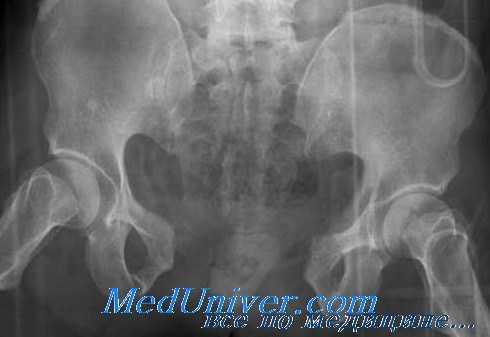

Вопрос о необходимости быстрого выявления пострадавших с переломами таза, имеющих высокую степень риска в отношении тазового кровотечения, не требует обсуждений. Установить локализацию источника кровотечения могут помочь сведения, касающиеся характера повреждения, а, следовательно, механизма травмы. Как правило, повреждение, приводящее к увеличению объема таза (АР или «открытая книга»), более вероятно вызовет значительное тазовое кровотечение по сравнению с повреждением, уменьшающим его объем (LC).

Тяжелые АР повреждения в большинстве случаев сопровождаются значительной кровопотерей. Если механизм травмы известен, нетрудно представить тяжесть перелома, что имеет, по-видимому, прямое отношение к объему кровопотери. Повреждения с полным отрывом половины таза сопровождаются самым сильным кровотечением и могут привести к падению АД.

Переломы могут быть единственной причиной кровотечения, или кровопотеря может быть комбинированной, когда дополнительный источник кровотечения находится за пределами таза, чаще всего в брюшной полости. Наиболее вероятным источником кровопотери при таких переломах будет кровоточащая поверхность зоны перелома и/или диффузное кровотечение из поврежденного венозного сплетения. Диффузное кровотечение может быть артериальным, например, при повреждении ветвей половых или запирательных артерий. Переднезадняя компрессия дает впечатляющее рентгенологическое изображение.

Но, даже при внимательном изучении снимков отрыв небольшого фрагмента заднего таза может быть пропущен, особенно в случаях состоявшегося наружного остеосинтеза. Moreo et al. проанализировали 92 случая переломов таза с переливанием более 6 доз крови за 24 часа, и оказалось, что у 28% больных был только односторонний перелом переднего таза, обнаруженный при обзорной рентгенографии. Столь необычный показатель (трансфузии) для казалось бы незначительных переломов авторы объяснили тем, что они были частью повреждений задней части таза, особенно связок. Объем трансфузии в этих случаях составил в среднем 11,2 доз.